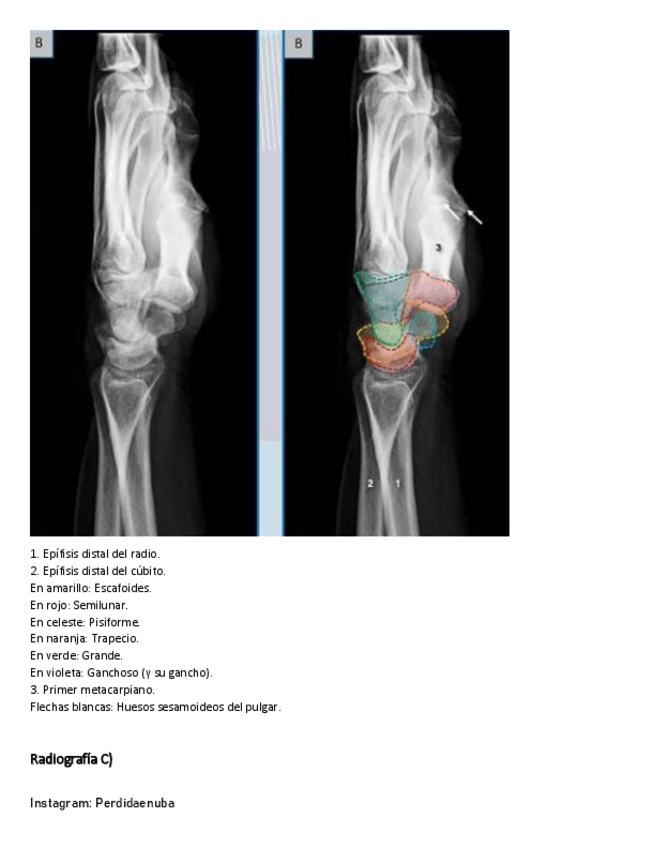

He publicado nuevos apuntes de 8º Cirugía General: CINTURA-PECTORAL-1.pdf